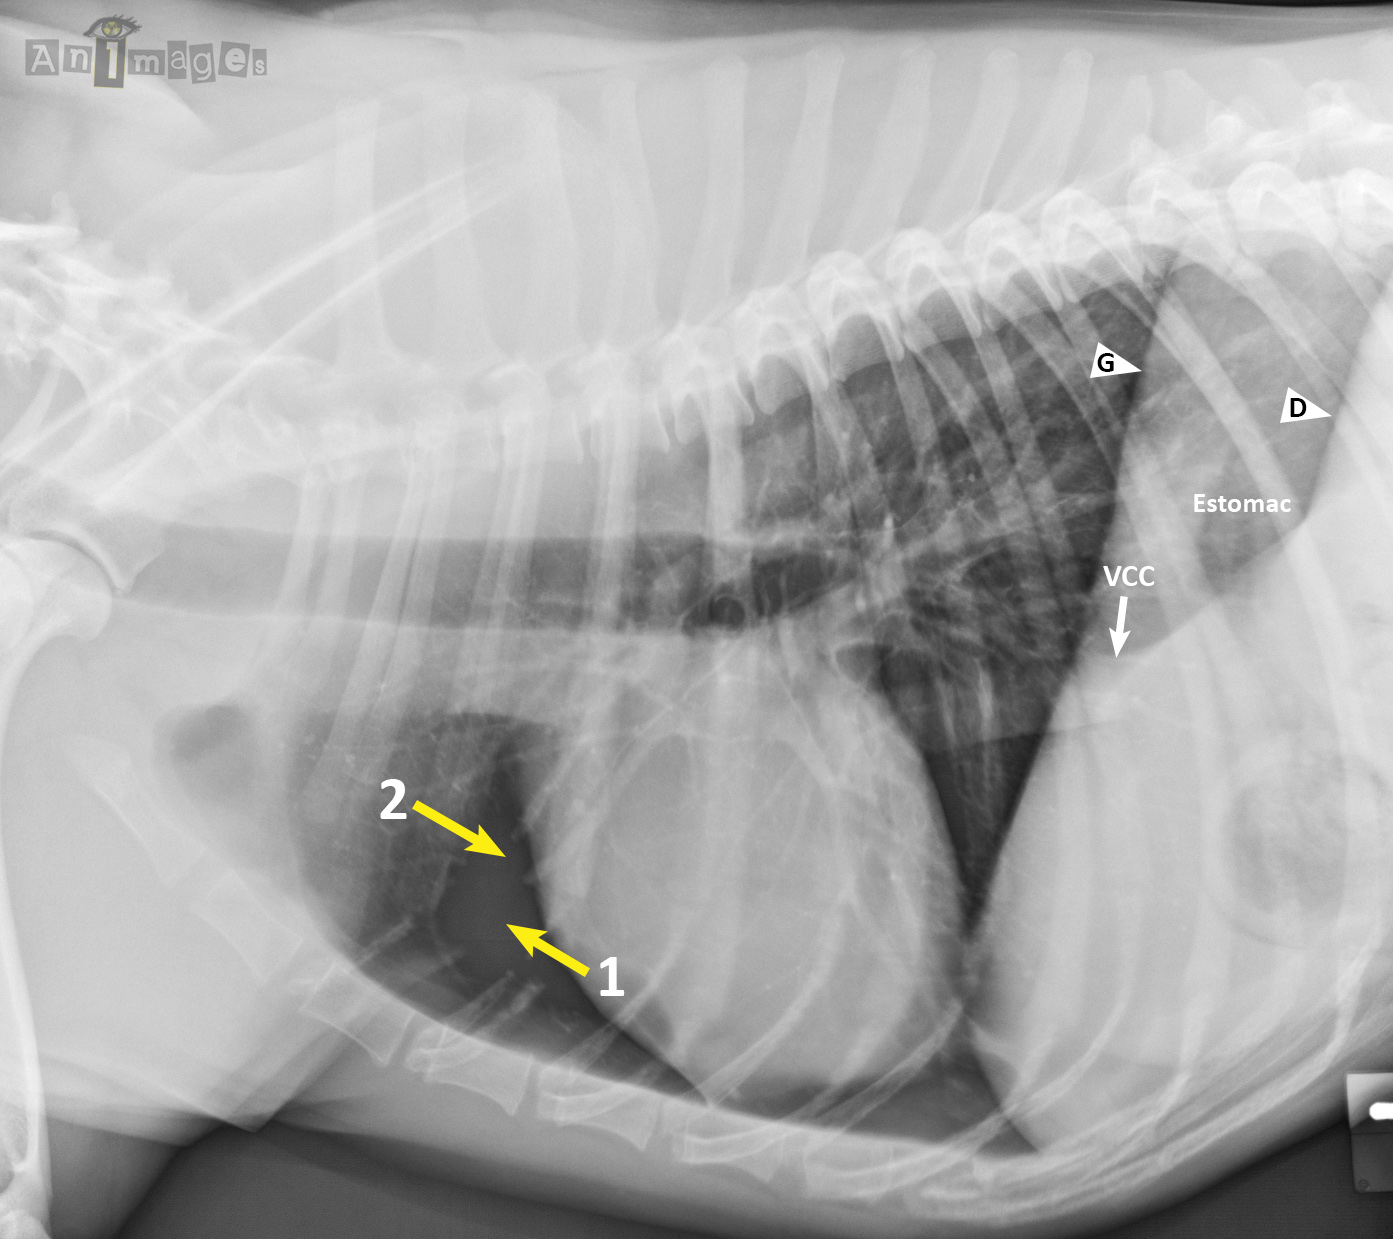

Cette projection a bien été prise en décubitus latéral gauche, ce qui est prouvé par l’apparence des piliers diaphragmatiques. En effet, le pilier gauche (G) est plus crânial que le droit (D), ce qui est attendu lorsque l’animal est couché sur son côté gauche et que son poumon est affaissé par le poids des structures médiastinales. On aperçoit aussi une partie du fondus de l’estomac entre ces deux piliers (celui-ci étant normalement caudal au pilier gauche) et la veine cave caudale (VCC) qui disparaît au 2e pilier seulement, soit le droit. Finalement, les piliers forment un « Y », typique d’une latérale gauche (les piliers étant parallèles sur une latérale droite).

Ce qui cloche plutôt est la perte complète d’information en portion crânioventrale des poumons. Le parenchyme à cet endroit n’est plus visible, laissant une plage complètement noire (1), et les vaisseaux pulmonaires tronqués (2). Ce phénomène a été provoqué par une surexposition qui a complètement saturé le détecteur numérique dans cette zone à plus faible atténuation. Le haut de l’image (i.e. colonne vertébrale) parait un peu pâlotte sur cette image, mais ceci s’explique plus probablement par une brillance de l’image ajustée à la hausse sur la station radiographique. Elle n’a donc rien à avoir avec un manque d’exposition, contrairement à l’apparence d’une sous-exposition sur une radiographie analogique ou conventionnelle (film).